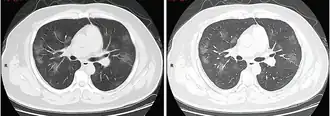

КТ грудной клетки иногда может помочь идентифицировать и охарактеризовать патологию лёгких и дать неспецифические результаты при инфекции COVID-19. Систематический обзор результатов компьютерной томографии грудной клетки у 919 пациентов описал типичное раннее проявление COVID-19 как «двустороннее мультилобарное помутнение матового стекла (GGO) с периферическим или задним распределением».[19] Одно исследование показало, что чувствительность КТ к инфекции COVID-19 составила 98 % по сравнению с чувствительностью ОТ-ПЦР на 71 %; однако это было сделано в китайской провинции Ухань и не подлежит обобщению.[20] Наиболее распространёнными результатами компьютерной томографии были двустороннее затухание матового стекла (пятнистое или рассеянное) с субплевральным доминированием, сумасшедшей укладкой и консолидацией на более поздних стадиях.[21] Эти данные являются неспецифичными и обнаруживаются также при других типах пневмонии. Небольшое исследование показало, что китайские рентгенологи продемонстрировали чувствительность 72-94 % и 24-94 % в дифференцировании COVID-19 от других типов вирусной пневмонии с использованием компьютерной томографии.[22] Ни одно исследование ещё не подтвердило точность и дискриминационную ценность компьютерных томографий, чтобы отличить COVID-19 от других вирусных пневмоний. Поэтому CDC не рекомендует КТ для первоначального скрининга, как подчёркивалось в звонке COCA в четверг, 5 марта. Люди с подозрением на COVID-19 должны проходить ОТ-ПЦР, которая является наиболее специфическим тестом.[23]

Компьютерная томография стадии быстрого прогрессирования